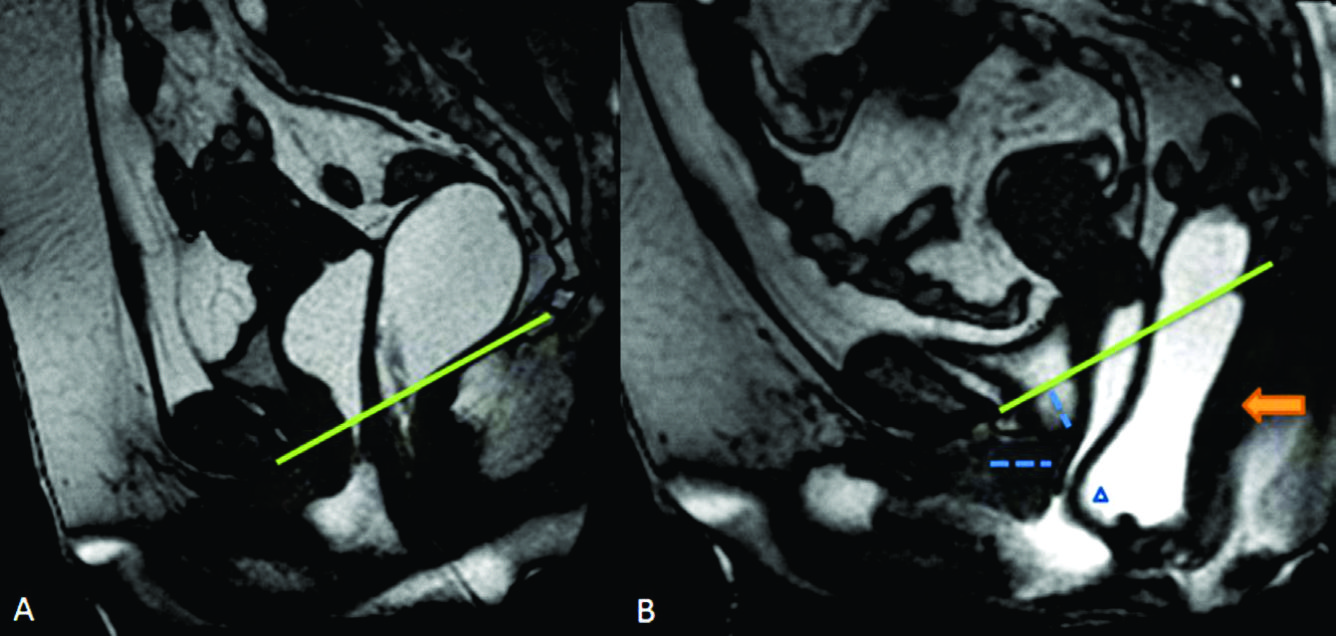

Figura 1

Evaluación anatómica. Líneas de referencia usadas para la valoración de la debilidad del piso pélvico. Imágenes potenciadas en T2 de alta resolución en el plano sagital a nivel de la línea media de una mujer durante el reposo. Recto distendido con gel ecográfico tibio. El útero no es bien visualizado dada su situación para mediana. A) PCL: Línea pubo-coccígea (línea continua). B) MLP: Línea media púbica (línea continua). Para evaluar el prolapso de los órganos pélvicos se trazan líneas perpendiculares desde los puntos de referencia anatómicos en los compartimentos anterior, medio y posterior hasta la línea PCL y/o MLP.

Figura 2

Líneas de referencia. Imagen de la línea media potenciada en T2 en el plano sagital, durante el reposo. Se trazaron la línea PCL (línea continua azul), línea H (línea punteada naranja) y línea M (línea punteada celeste). El músculo puborectal se topografía inmediatamente por detrás de la unión ano-rectal y el plano del elevador es paralelo a la línea PCL.

La valoración del piso pélvico se hace mediante la valoración morfológica, el sistema HMO y el ángulo ano rectal (Ver figuras 1, 2 y 3) (1)

La valoración morfológica se realiza con secuencias potenciadas en T2 de alta resolución, que permiten un estudio anatómico detallado de los órganos de la pelvis. El sistema HMO constituye un método estandarizado creado para caracterizar y documentar el prolapso y relajación del piso pélvico, que se basa en el trazado de tres líneas fundamentales.

La línea pubococcígea (PCL) se extiende desde el borde inferior del pubis a la última articulación coccígea y representa el nivel de piso pélvico, constituyendo la línea de referencia a partir de la cual se miden los prolapsos, tanto en reposo como en Valsalva.

La línea H se traza desde el borde inferior del pubis hasta la pared posterior del recto a la altura de la unión ano rectal, representando el diámetro anteroposterior del hiato urogenital, con un valor normal menor a 6 cm (Ver figuras 4).

La línea M es perpendicular a la PCL a nivel del sector más posterior de la línea H y representa el descenso del hiato del elevador, con un valor normal menor a 2 cm. El ángulo ano rectal es el ángulo entre el eje central del canal anal y la pared posterior del recto, con un valor normal entre 108º y 127º y una variación de hasta 15º en Valsalva.

Se describe una línea adicional llamada línea media púbica (MPL) que se traza caudalmente siguiendo el eje mayor de la sínfisis del pubis. Esta línea corresponde al nivel del himen vaginal, el cual es utilizado históricamente como punto de referencia para la valoración clínica. 12-13